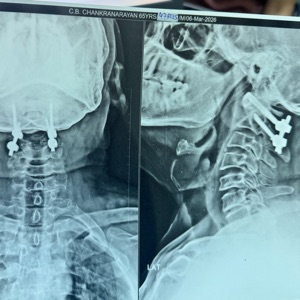

Spinal trauma management involves surgical and non-surgical interventions to stabilize the spine and protect neural elements. Techniques include instrumentation with rods, screws, and plates, spinal fusion, and in some cases, vertebroplasty or kyphoplasty for vertebral compression fractures. The approach depends on injury severity, location, and neurological involvement, aiming to restore spinal alignment and function.